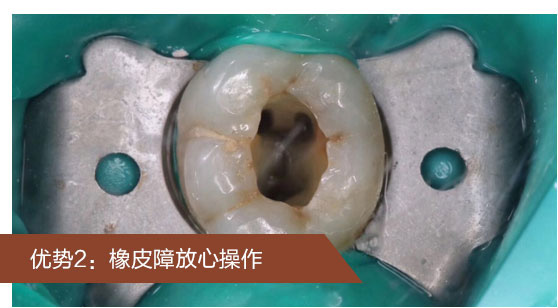

①橡皮障隔离状态下易保持治疗过程无菌

②保护其他牙齿受到患牙细菌的污染

③保护器械对唇、舌等口腔软组织造成意外损失